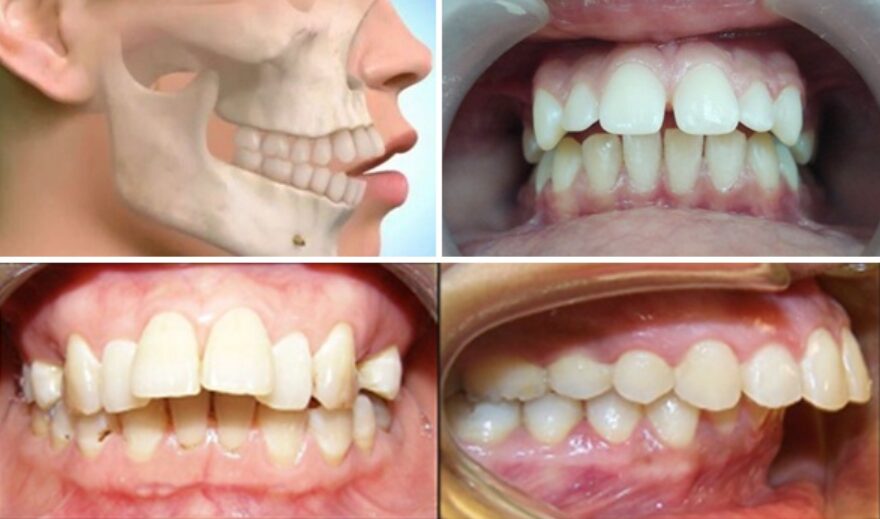

Răng hô, hay còn gọi là tình trạng sai lệch khớp cắn loại II trong tiêu chuẩn nha khoa. Đây là một trong những dạng lệch lạc răng phổ biến, chiếm khoảng 20–30% dân số. Biểu hiện đặc trưng của răng hô là cung hàm trên phát triển vượt trội. Điều này khác biệt hẳn về phía trước so với cung hàm dưới. Từ đó gây ra sự mất cân đối trong cấu trúc khuôn mặt.

Răng hô hàm trên là tình trạng mà răng hoặc xương hàm trên (hoặc cả hai) phát triển nhô ra quá mức so với hàm dưới. Thông qua đó gây ra sự mất cân đối trong khớp cắn và khuôn mặt. Đây là một dạng sai lệch khớp cắn phổ biến, thường kèm theo các biểu hiện sau:

Răng hô kèm cằm lẹm

Răng hô cằm lẹm là dạng sai lệch phức tạp. Hiện tượng này xảy ra khi xương hàm trên phát triển quá mức. Cùng với đó xương hàm phía dưới phát triển kém. Cằm bị đẩy lùi sâu vào trong, gây mất cân đối tổng thể gương mặt. Các dấu hiệu thường thấy bao gồm: